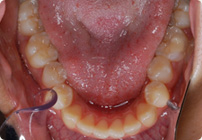

Caso: 19 años

Adulto: Clase III

Mordida Abierta Anterior

Mordida Cruzada Anterior y Posterior

Endo necesitado para #19

Extract U5’s, LR4, LL6

6 alambres superiores

5 alambres inferiores

Elásticos Clase III 2oz. TP Verde

Retenedores: Interior Fijo de TMA y Hawley en superior

Tiempo de tratamiento: 21 Visitas